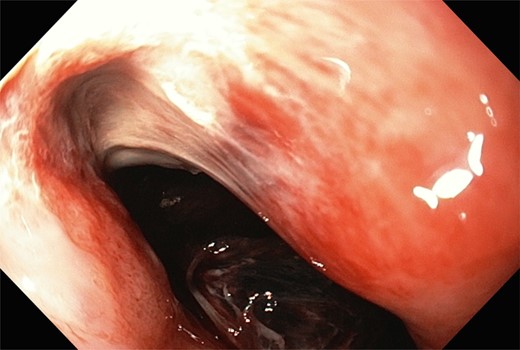

A 60-year-old female was admitted for management of hematemesis. Three weeks prior, she sustained a flail chest, right hemothorax, splenic laceration, mesenteric injury, and lumbar and thoracic vertebral fractures in a motor-vehicle accident. She initially underwent a trauma laparotomy and right hemicolectomy. Significant hematemesis occurred 4 days after admission to the rehabilitation ward, and the patient was transferred to the intensive care unit (ICU), where a gastroscopy was performed. A large clot was observed in the fundus; however, there was no active bleeding. A Sengstaken–Blakemore (SB) tube was inserted and the gastric balloon inflated under endoscopic vision, and 6 units of packed red blood cells, 4 units of fresh frozen plasma, 2 units of platelets and 10 units of cryoprecipitate were transfused. Hemodynamic stabilization was achieved, and serum hemoglobin rose from 61 to 89 g/dl . A repeat gastroscopy the following day demonstrated the fundal clot plus a large MWT at gastroesophageal junction (GEJ) (Fig. 1). Adrenaline (1:10 000) was injected around the tear, and the SB tube was removed. The patient subsequently developed a pulmonary embolism, which was treated with an inferior vena caval filter. On Day 5 after transfer to the ICU, the patient was discharged to the regular ward. She was receiving proton pump inhibitor (PPI) therapy. Hematemesis recurred on Day 8, and the patient was intubated because of hemodynamic instability. Gastroscopy was performed after massive transfusion resuscitation, and the large fundal clot and MWT were again noted. Hemostatic powder (EndoClot®) was applied over the probable location of the fundal ulcer as well as MWT though there was no active bleeding.

A large Mallory–Weiss tear and large fundal clot were observed during gastroscopy.